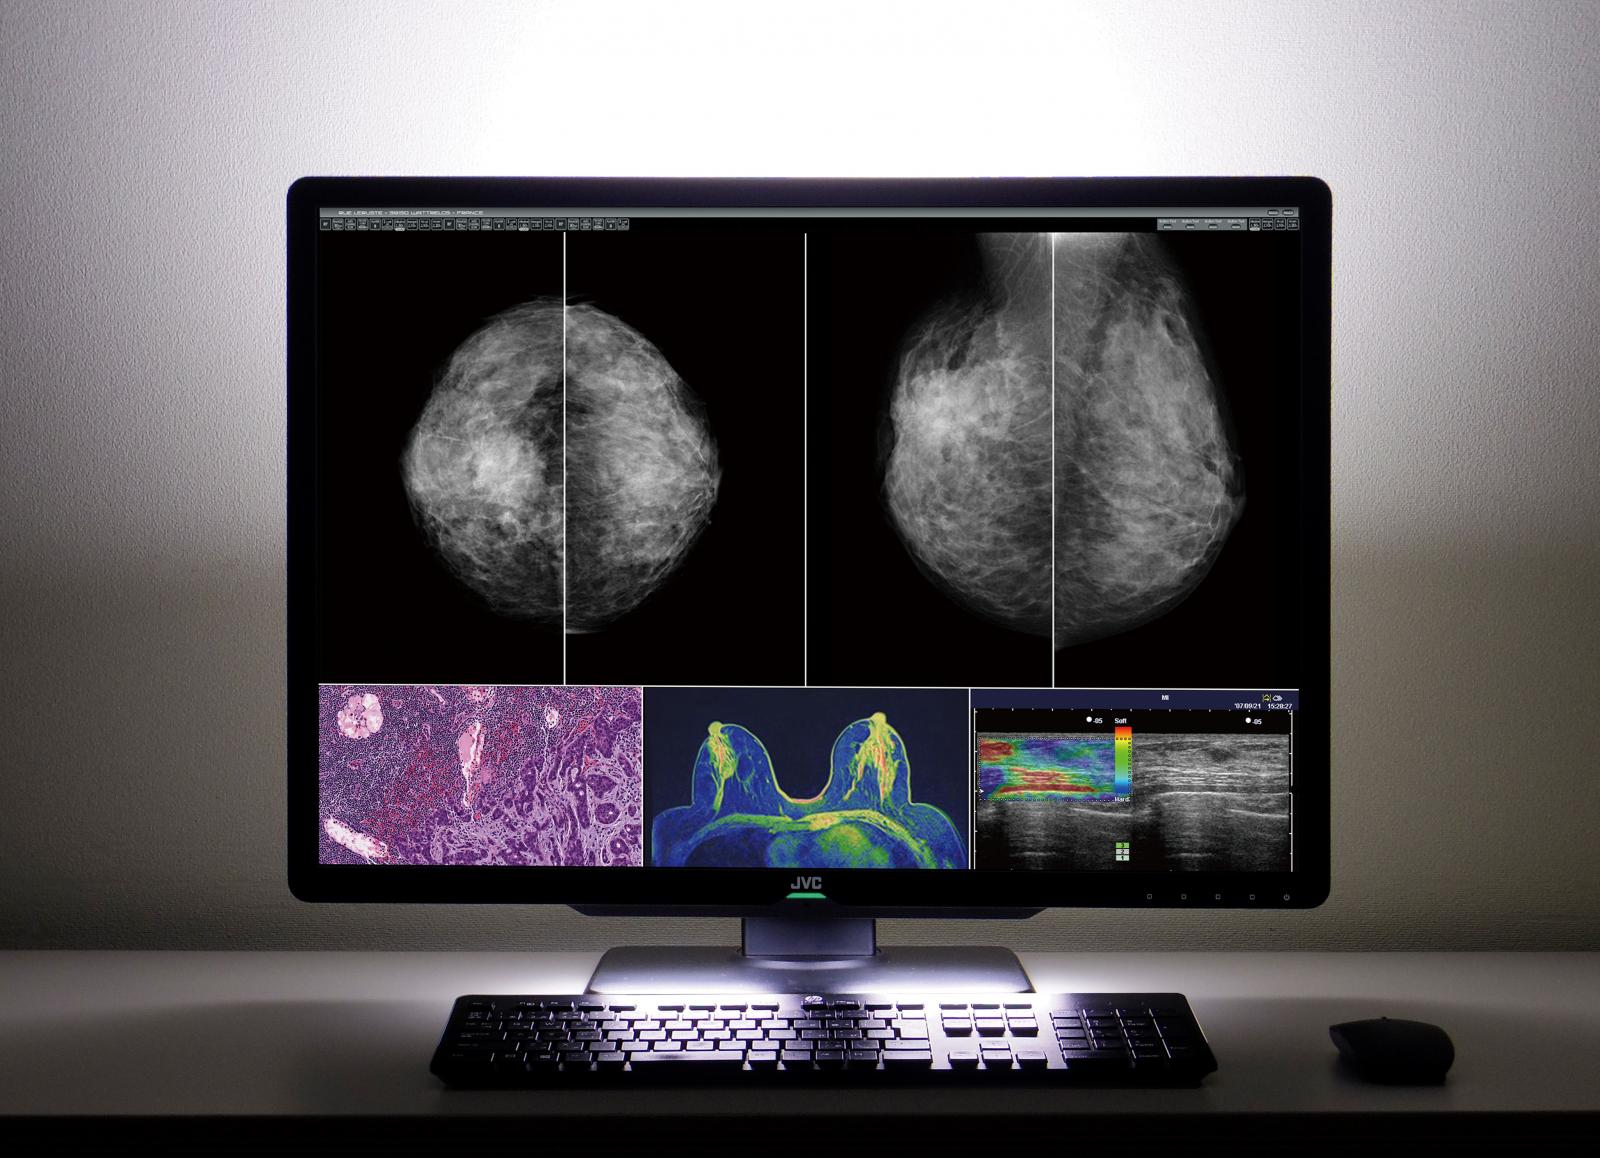

Afficher des images médicales de différentes modalités comme le scanner, la CR/DR, l’IRM, l’échographie ou la mammographie et la pathologie sur un seul écran – c’est ce que souhaitent la plupart des radiologues. En effet, nombre d’entre eux utilisent encore aujourd’hui plusieurs écrans médicaux côte à côte. JVCKENWOOD rend cela superflu avec son nouveau moniteur couleur de 30,9 pouces CL-S1200. L’appareil de 12 mégapixels (4.200 horizontaux et 2.800 verticaux) peut afficher différentes images médicales côte à côte. La disposition des fenêtres peut être choisie librement et le grand écran sans barre centrale crée un environnement confortable pour les diagnostics radiologiques. Avec une luminosité maximale de 1200 cd/m² et un rapport de contraste de 1500:1, il est également adapté à la mammographie.

La nouvelle fonction de turboluminescence peut augmenter la luminosité de l’écran jusqu’à 1000cd/m² afin d’agrandir les niveaux de gris reconnaissables. Le radiologue peut ainsi évaluer en toute sécurité les lésions à faible contraste sur les mammographies. L’effet est encore renforcé par le mode Visual Point.